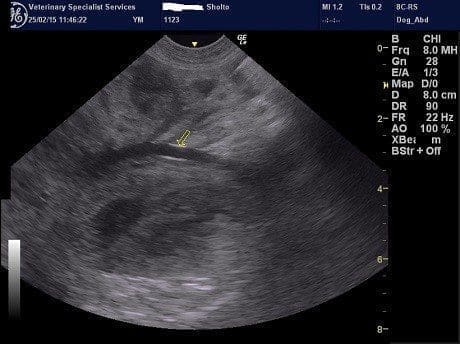

The transverse colonic wall was markedly thickened (>1cm) (pic). A large mass with irregular borders and mixed echogenicity was identified in the mid dorsal abdomen (pic). This mass was situated just cranial to the kidneys. The mass was well supplied with blood vessels, some of which were very large (pic). The mass was closely approximated with the abnormal piece of transverse colon. The origin of this mass was not identified on ultrasound due to its size so advanced imaging using MRI was performed.